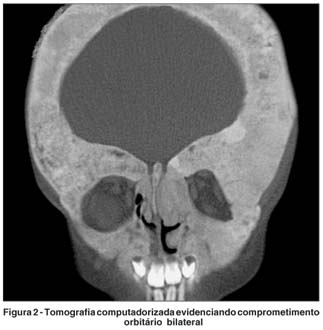

Apesar da relativa normalidade do exame oftalmológico, uma tomografia computadorizada de crânio e face foi solicitada, cujo resultado revelou importante comprometimento orbitário circunferencial bilateral englobando todas as paredes orbitárias, inclusive as regiões apicais (Figura 2).

A tomografia computadorizada de crânio e face, de preferência com janela óssea, é sempre necessária para a avaliação de pacientes com DF, mesmo nos casos que aparentemente não apresentam grandes acometimentos orbitários.